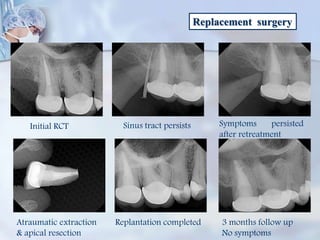

Replacement surgery

Initial RCT Sinus tract persists Symptoms persisted

after retreatment

Atraumatic extraction

& apical resection

Replantation completed 3 months follow up

No symptoms